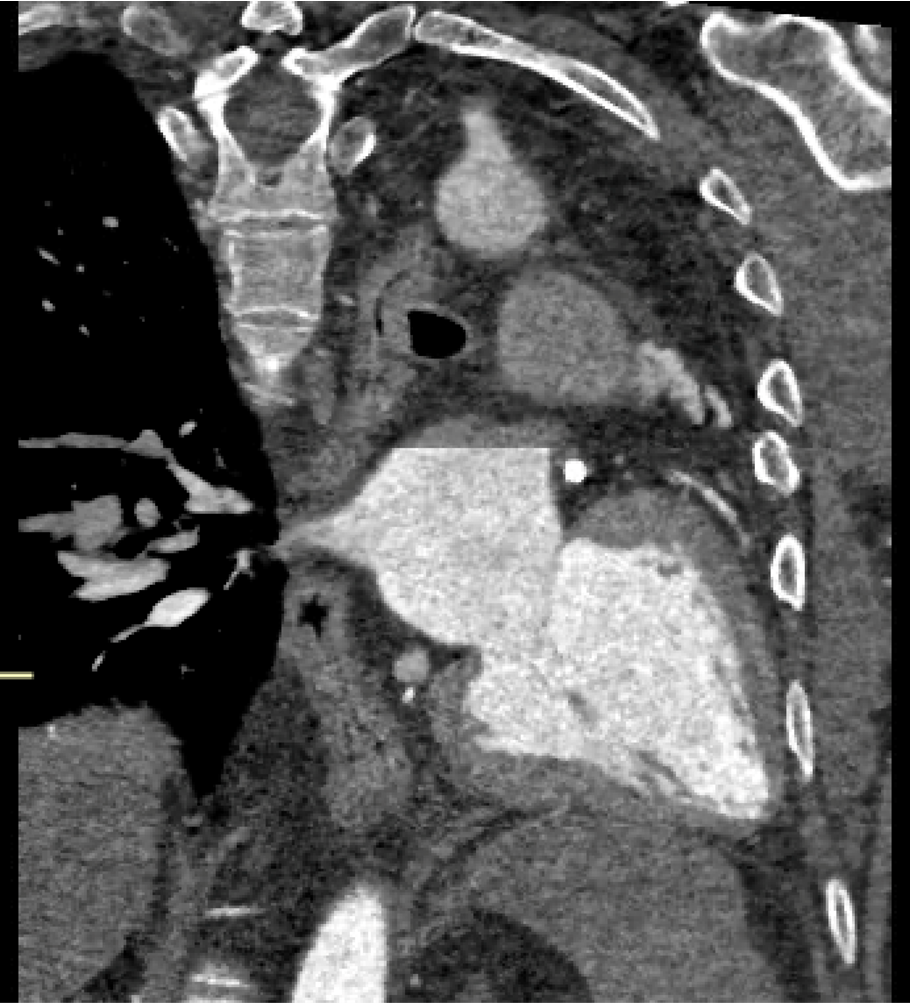

61 year old male presenting with unstable angina and CTO of the LAD

Previous left pneumonectomy for typical carcinoid tumour 2001

Angio: CTO of proximal LAD with filling from RCA, Patent LCx stent, 60% Mid LCx stenosis distal to stent (DFR 1.0), Mild disease proximal RCA